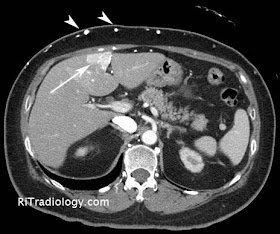

| An axial CT image shows a geographic area of hypervascularity (arrow) in segment IV of the liver. Note enlarged subcutaneous collateral vessels (arrowheads) |

Facts: Focal Hepatic Hot Spot

- Focal area of enhancement in segment IV of liver due to presence of SVC obstruction

- Occurs due to portosystemic shunting between SVC and portal vein

- With SVC obstruction, blood may flow through internal mammary vein --> paraumbilical vein --> portal vein